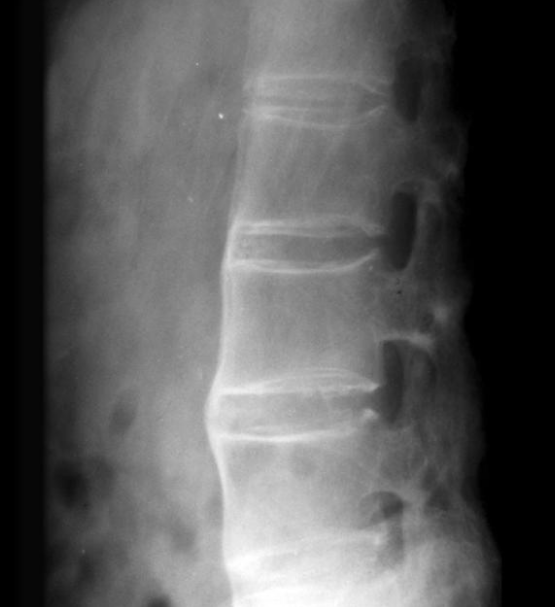

Oblique 촬영

- 관절간 이상을 평가하기 가장 좋은 방법. 특히 후관절(facet joint)

- 잘 촬영된 Obl 사진은 scotty dog sign 관찰 가능.

- 디텍터에 가까운쪽 관절 관찰이 용이하다